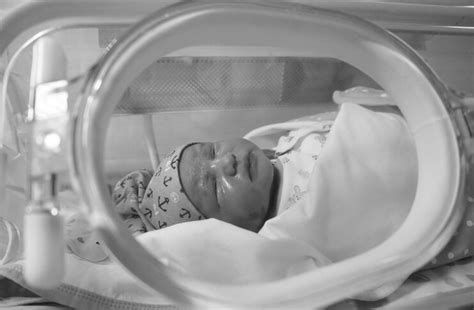

Copiii născuți prematur necesită, de obicei, îngrijiri medicale specializate într-o unitate de terapie intensivă neonatală (UTIN). Neonatologii sunt specializați în îngrijirea acestor nou-născuți, care pot necesita suport pentru respirație, hrănire, menținerea temperaturii corporale și alte funcții vitale. Durata spitalizării depinde de greutatea la naștere, capacitatea de a respira independent, nevoile de hrănire și starea generală de sănătate.

Un copil prematur este, de obicei, externat atunci când atinge o greutate normală pentru un nou-născut (peste 3 kg), poate fi alăptat sau hrănit prin biberon, respiră fără probleme și își reglează singur temperatura corporală. Majoritatea prematurilor necesită controale medicale suplimentare pentru monitorizarea creșterii și dezvoltării.